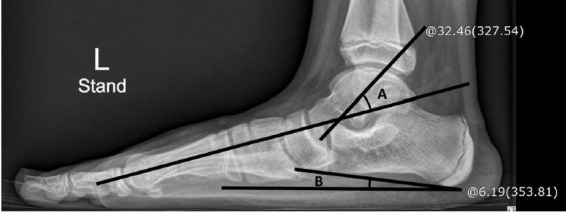

Results: A total of 52 subjects was included in the plantar pressure analysis, with a mean age of 9.9 years at the first visit and a median follow-up duration of 52 months. The lateral tarso-first metatarsal angle decreased by 1.3° (p<0.001) and calcaneal inclination angle increased by 2.5° (p<0.001) in these patients. The percentage value of midfoot width (WMF) divided by forefoot width (WFF) decreased by an average of 9.8% p (p<0.001), and the maximal pressure on the medial midfoot (MMF) decreased by 1.6 N/cm2 (p<0.001). However, no correlations were found between plantar pressure and radiographic changes.

Conclusion: During follow-up of patients with FFF, the maximal pressure on the MMF and the ratio of WMF to WFF decreased in successive plantar pressure examinations. Changes observed in plantar pressure and plain radiographs were not consistent, indicating that these two testing modalities can complement each other.